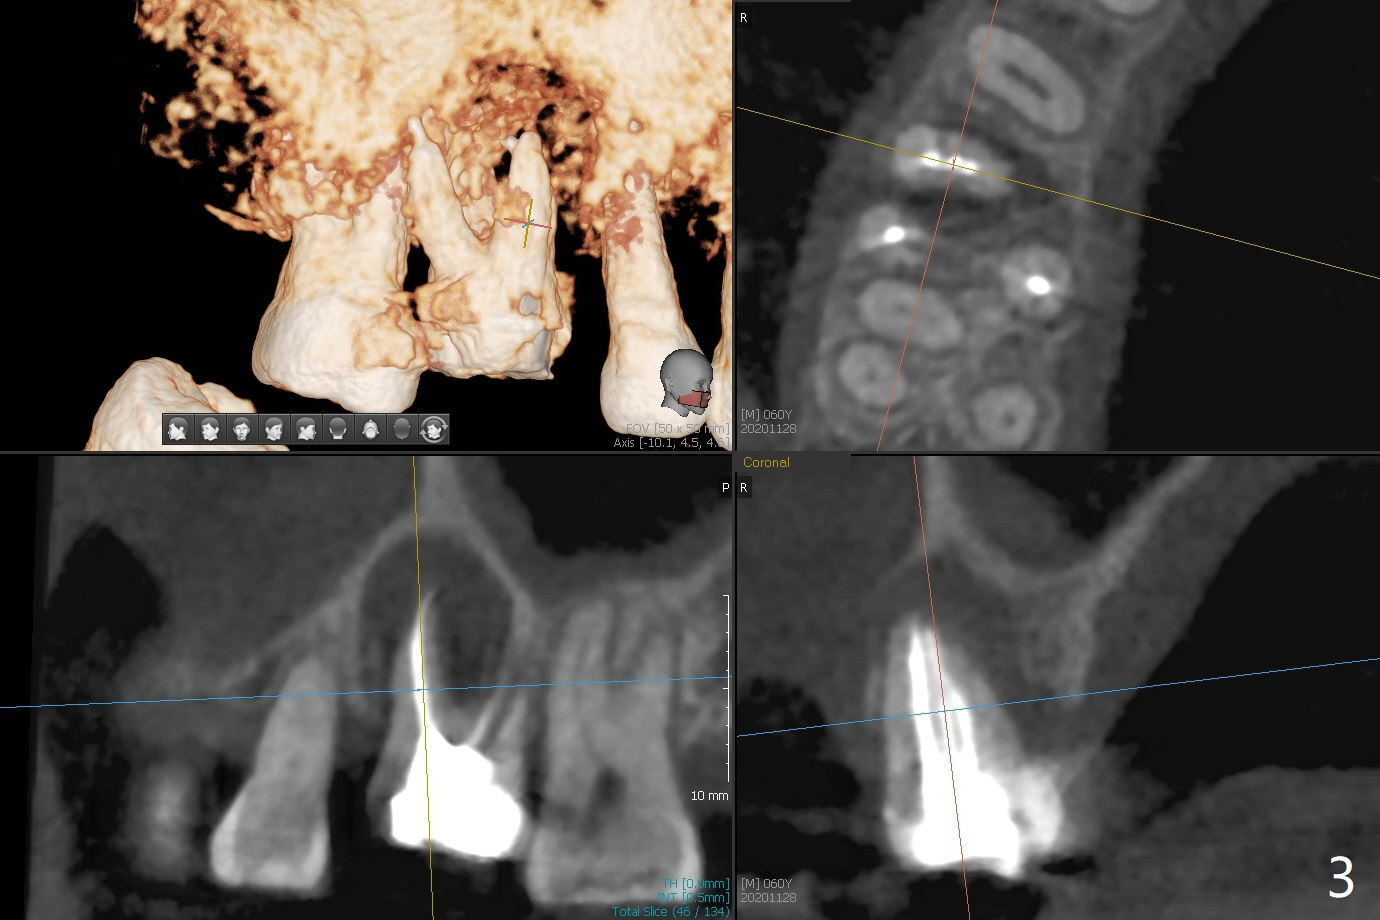

60岁男右上6出现脓包(图一),颊侧牙周袋深9毫米,指向近中颊侧根尖,根尖片(图二)和CT(图三(去除牙冠后))显示巨大近中颊侧根周骨质吸收,但是松动度低,一度想做根切。最佳植牙位点偏远中腭侧(图四),植体偏小,稳定性差,使用临时基台制作牙合面低的临时牙冠,目的包括固定粘性骨粉和防止邻牙移位。半张PRF膜用于上颌窦提升,另外半张用于覆盖牙槽窝开口的骨粉。局部使用抗菌素(Arestin),十九天后瘘道消失,根切,植骨可能成功。